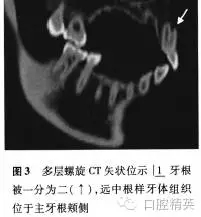

根尖X線片示:|1牙根被縱向線狀投射影分為近中和遠(yuǎn)中兩個牙根,遠(yuǎn)中牙根根尖牙周膜增寬,疑似根折或雙牙根。為進(jìn)一步明確診斷,行多層螺旋CT(Somatom Sensation 16,西門子,德國)檢察,CT影像示:牙根唇面及舌面溝樣凹陷自牙頸部向根尖部逐漸加深,至根中1/3兩者貫通將牙根一分為二,遠(yuǎn)頰“額外根”內(nèi)未見低密度影像,提示“額外根”內(nèi)無牙髓組織,為實心牙體組織,“額外根”周圍可見低密度影像(圖1-3)。

多層螺旋CT顯示該牙根被兩個向根尖部逐漸加深的唇面溝和舌面溝在根中1/3分開,在主根管遠(yuǎn)頰側(cè)形成“額外根”,CT冠狀位、矢狀位及軸位影像顯示“額外根”中未見低密度影像深入,提示此“額外根”內(nèi)無牙髓組織,因此可以排除雙根管,確診是由于畸形根面溝造成的額外牙體組織突起。